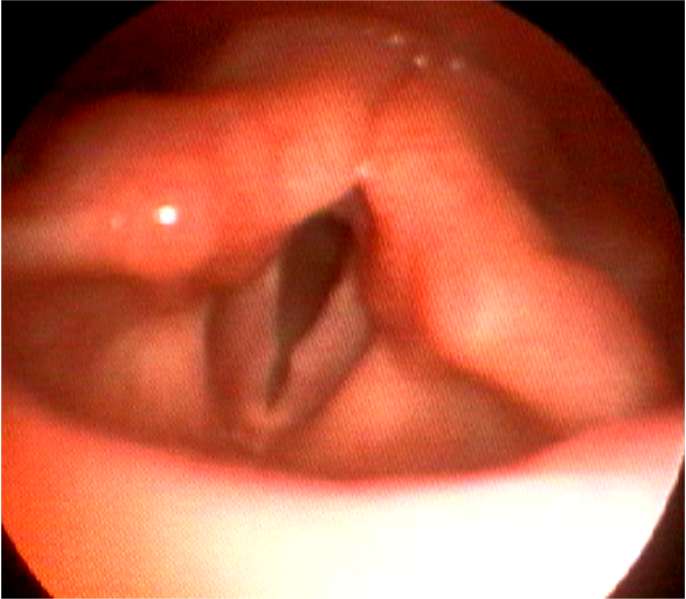

・声帯ポリープは声帯結節、声帯ポリープ、ポリープ様声帯の3種類にわけられます。

・声帯結節は声帯の前方1/3に両側性にできることが多く、小児では大声で話す男子によくみられ、成人では女性に多く発生します。

声帯結節